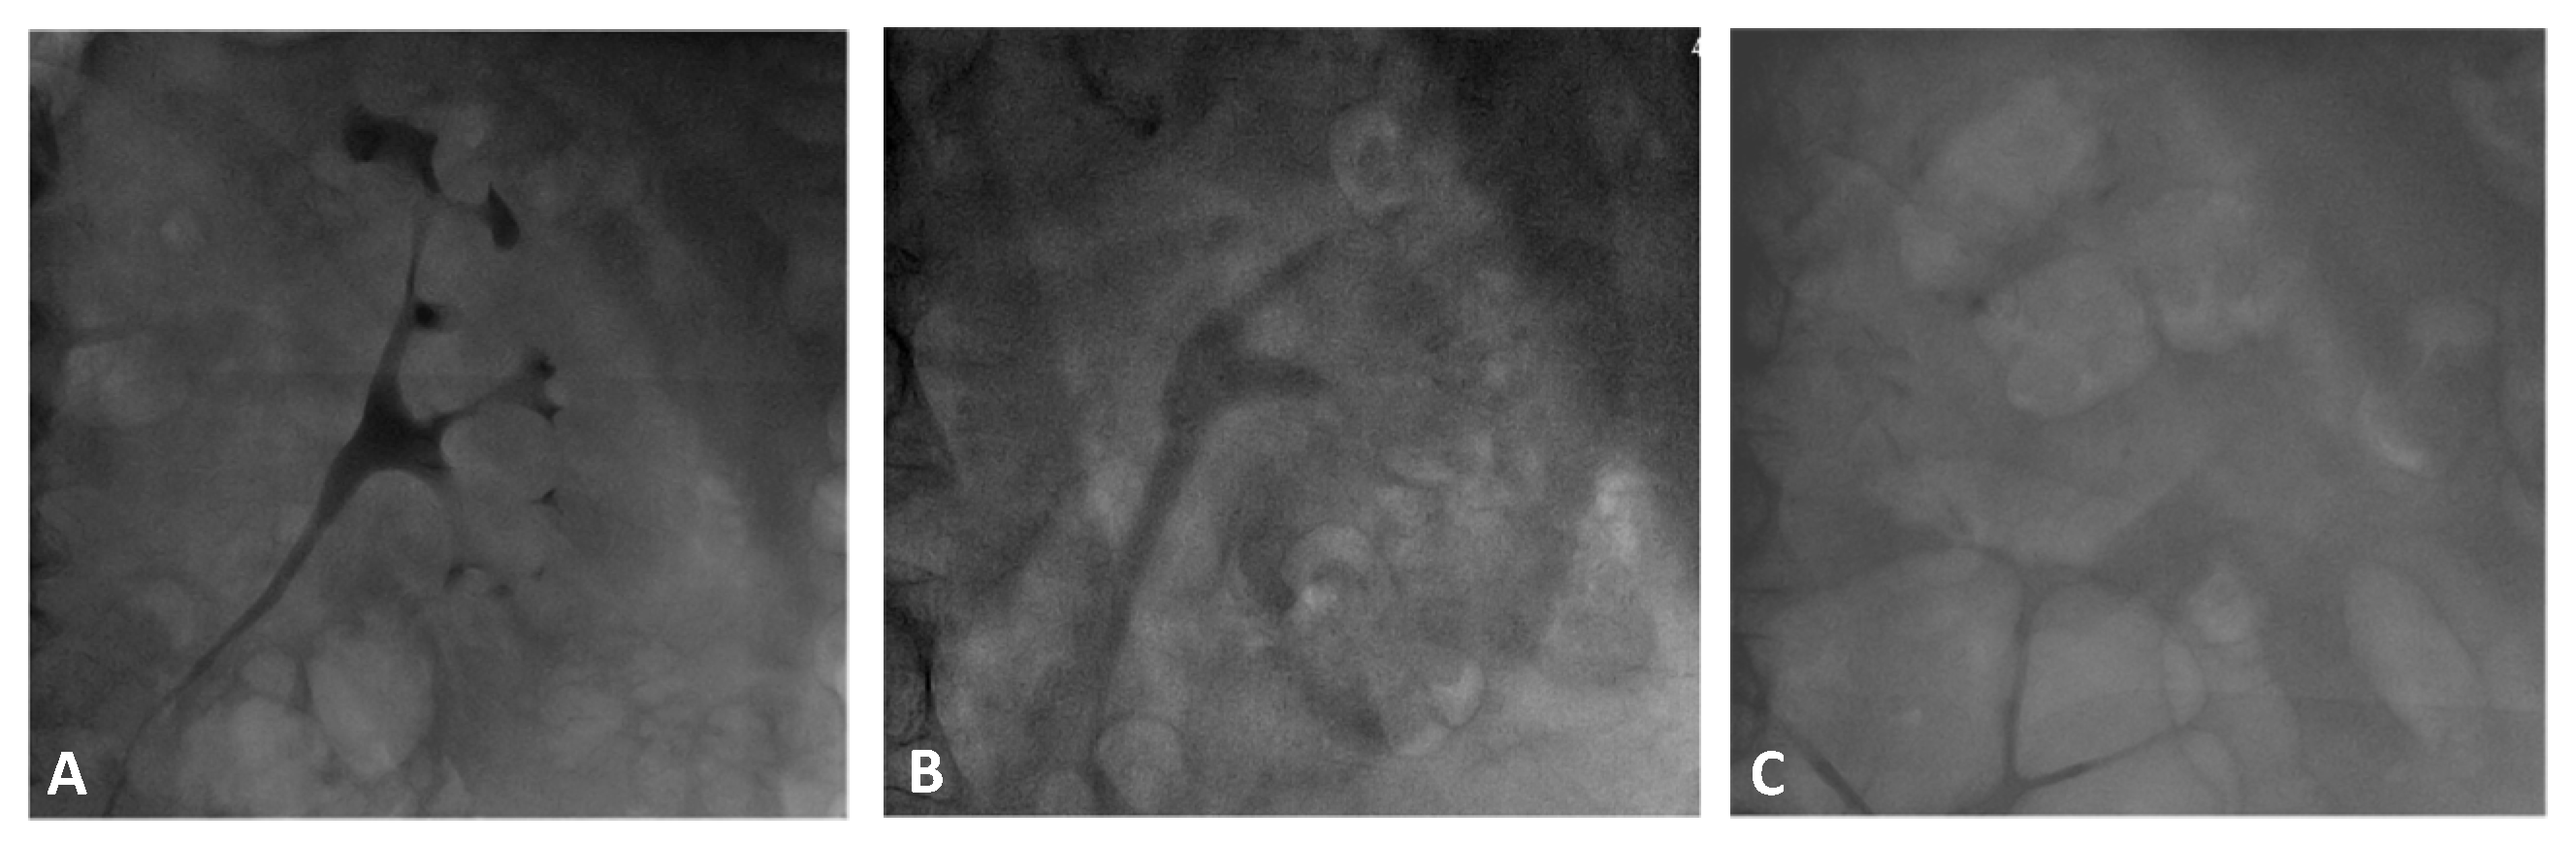

2.3. Renal Contrast Accumulation Analysis

3.2. Contrast Accumulation Score